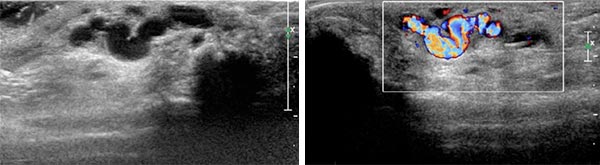

Ultrasound reveals a subcutaneous dilated drainage vein from the digital AVM at the third finger. Color-coded duplex ultrasound (CCDU) confirms the fast-flow arteriovenous shunt with high flow.

Since it seems technically impossible to treat the AVM via a transarterial approach alone for re-embolization, a percutaneous access route in the direct puncture technique is now selected under sonographic guidance.

Percutaneous ultrasound-guided advancement of the puncture needle into the drainage vein of the digital AVM.